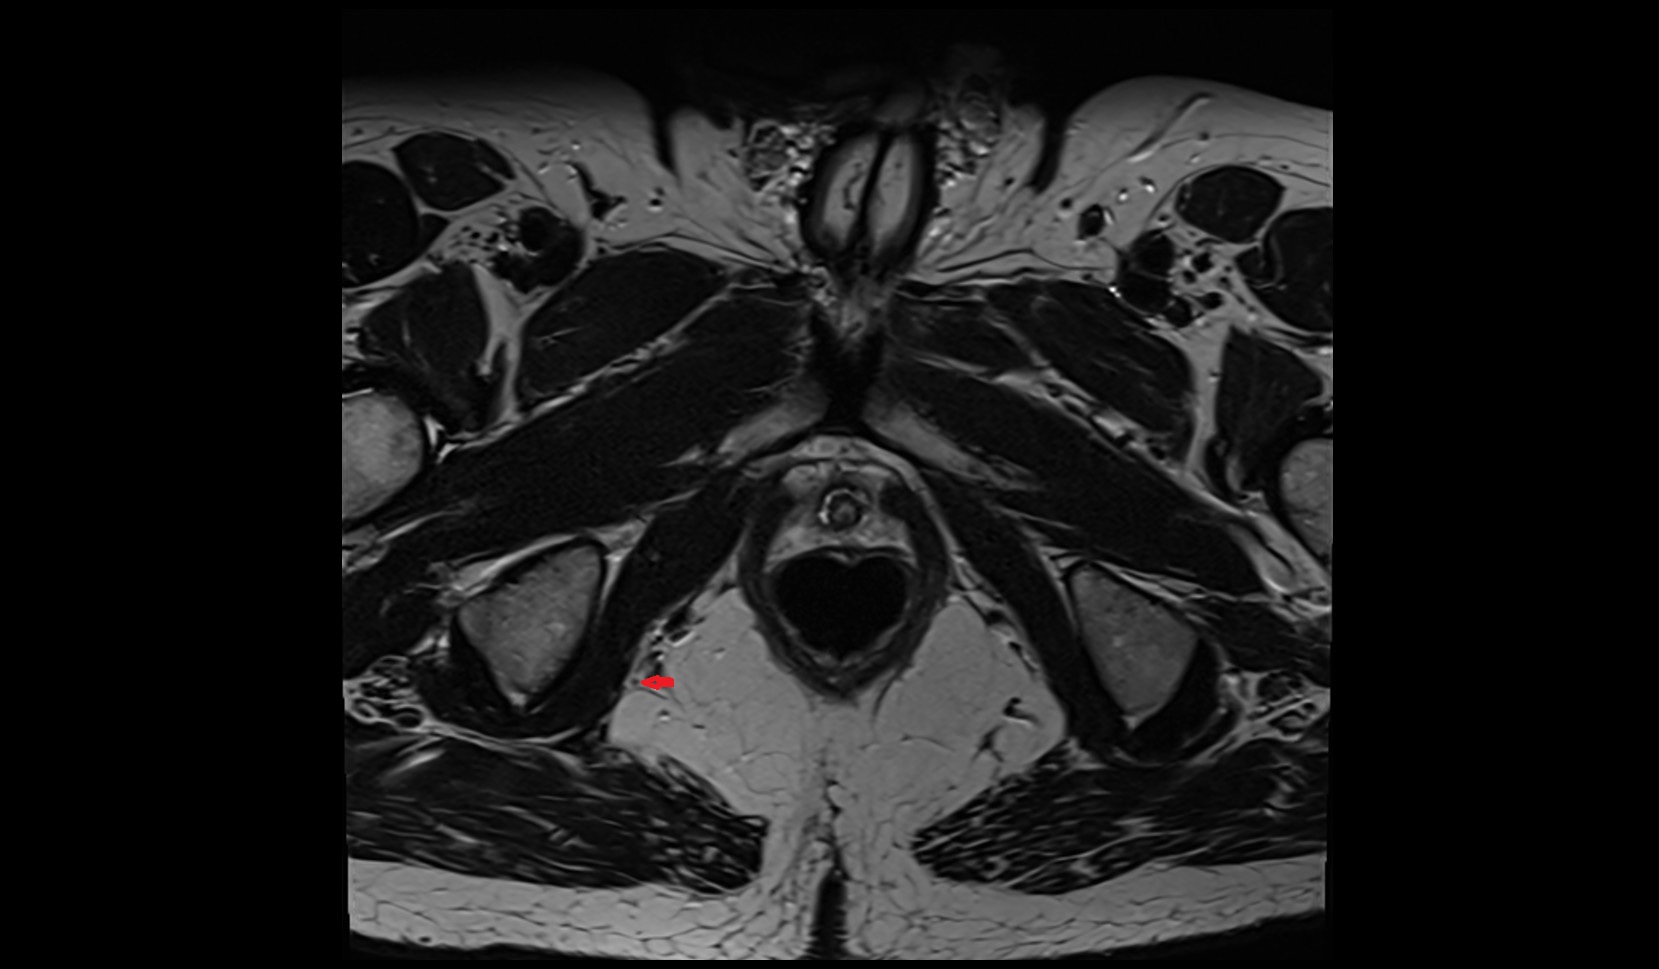

- Hip joint